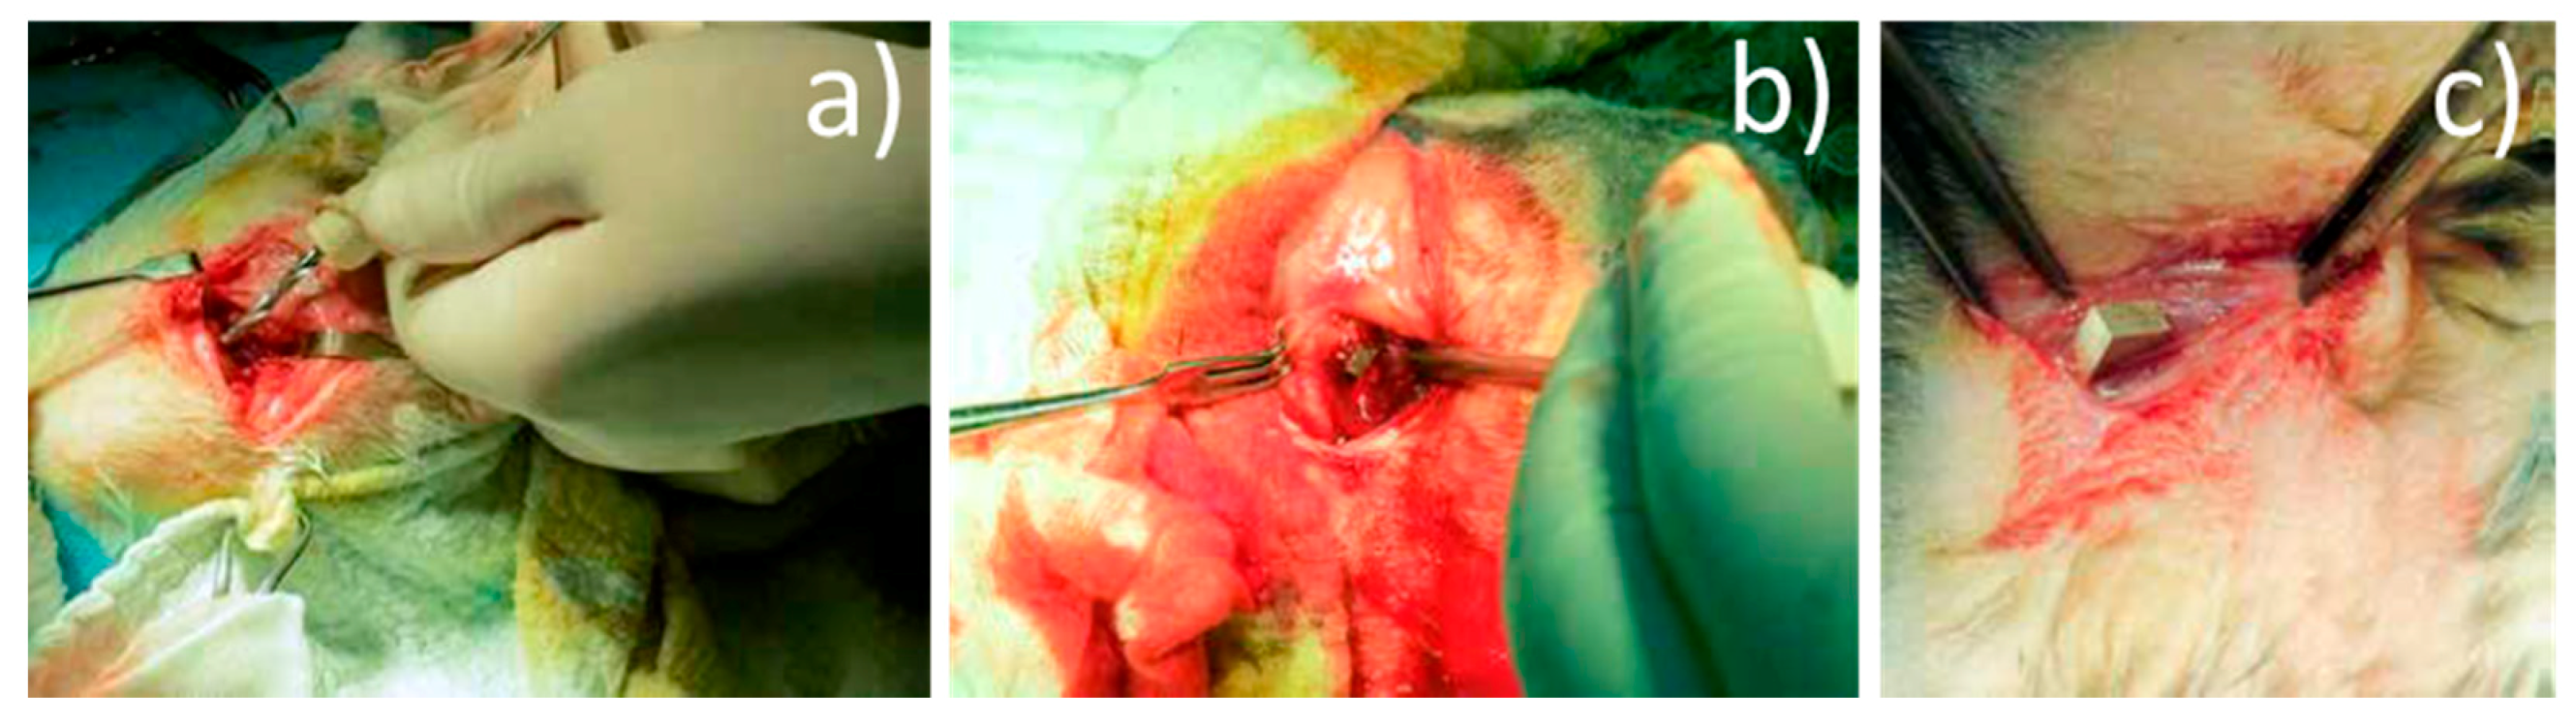

3.2.1. Radiological Follow-Up